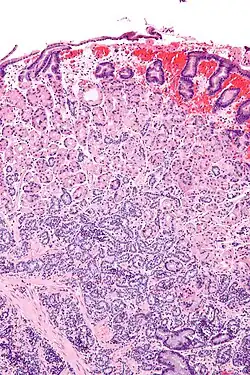

| Micrograph of a neuroendocrine tumour of the stomach. H&E stain. | |